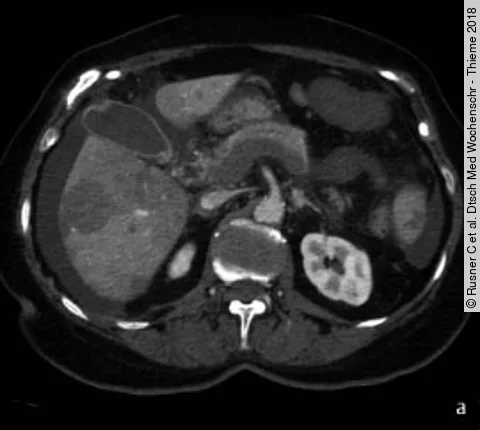

Quiz70-Jährige mit akutem Abdomen

Die 70-Jährige stellte sich mit dem klinischen Bild eines akuten Abdomens in der Notaufnahme vor. Sie gab progrediente Bauchschmerzen seit 5 Tagen an. Bei der klinischen Untersuchung ergaben sich abdominal eine diffuse Abwehrspannung und fehlende Darmgeräusche. Das Basislabor erbrachte keinen wegweisenden Befund. Es erfolgte eine…

QuizAuflösung: 70-Jährige mit akutem Abdomen

Befunde (s. Bildergalerie)

1. Thrombose der V. portae, V. lienalis und V. mesenterica superior

2. Akute Ischämie des Dünndarms

3. Perfusionsdefekte der Leber und Milz

4. Aszites